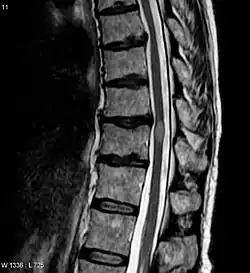

| An MRI showing a transverse myelitis lesion, which is lighter, oval shape at center-right. The patient recovered 3 months later. | |